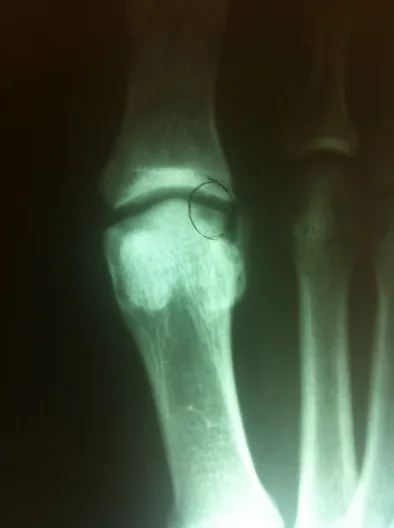

First MPJ OCD (Below)

Osteochondral Autograft Transfer System (O.A.T.S.)